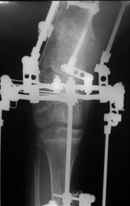

Диагноз: Дисхондроплазия. Варусная деформация дистального метафиза правой бедренной кости; состояние после оперативных вмешательств (1993 и1994 гг.).

Деформация правой нижней конечности с 6 месяцев (стала прогрессировать после года, с момента начала ходьбы). Поставлен диагноз болезнь Олье, варусная деформация, укорочение правой нижней конечности на 4,5 см. 1993 г. - операция остеоклазия на уровне очагов поражения в н/3 правой бедренной кости и в/3 правой большеберцовой кости с одномоментной коррекцией деформации и фиксацией костных фрагментов спицами Киршнера.После начала статической нагрузки (1994 г.) появился рецидив деформации и укорочения. Вторая операция - ЧКО АВФ, аппарат демонтирован через 2недели в связи с развившимся на уровне стержня переломом, после чего находилась в гипсовой повязке до консолидации костных фрагментов. Далеелечилась консервативно в гипсовой повязке. Выраженная деформация и укорочение правой нижней конечности. Относительная длина бедер: справа -34 см, слева - 51 см; анатомическая длина голеней: справа - 29 см, слева - 39 см. Величина варусной деформации на уровне дистального отдела правого бедра составляет - 80 град. Амплитуда движений в коленных суставах (разгибание/сгибание ): справа - 0/0/100 град.; слева - 0/0/30 град. Отмечается боковая и ротационная нестабильность на уровне правого коленного сустава. Амплитуда движений в голеностопных суставах - в норме. Тактика лечения? Заранее благодарю! С уважением,А.В.Владзимирский

Высылаю вам фото подобной больной, у нее тоже первая попытка до меня была безуспешной.

Нужен аппарат Илизарова стабильный с множеством спиц с напайкой, временной фиксацией колена аппаратом на голени. Наверное, проще первый раз начать с бедра, остеотомию выполнить прямо на уровне перехода очага в дистальный метафиз бедра. Дистракционный остеогенез вызовет перестройку хрящевой ткани в костную. Понадобится еще пара этапов.